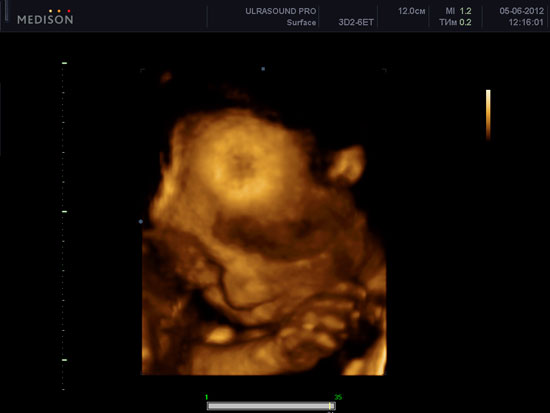

Перед тим, як відправити вас в передпологовій відпустку, лікар допоможе порекомендувати пройти УЗД плоду в 30 тижнів вагітності для того, щоб упевнитися нормальному розвитку плоду. За статистикою, 3D 4D УЗД при вагітності з 26 до 30 тижнів вагітності дає можливість отримати найбільш якісні знімки і відео вашого малюка. Постарайтеся не упустити цю унікальну можливість! Найбільш пізніх термінах діти частіше притискаються тісно до матки, навколоплідних вод ставати менше по відношенню до прогресивно зростаючого плоду, візуалізація гірше.

При УЗД плоду в 30 тижнів вагітності деякі діти смокчуть великий палець, що можуть споглядати батьки. Деяким дітям подобається терти очі, гладити себе по голові, кажучи:? Який же я хороший !?